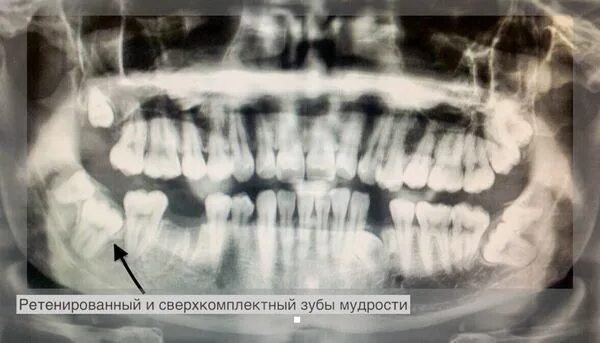

Дистопированный зуб мкб 10